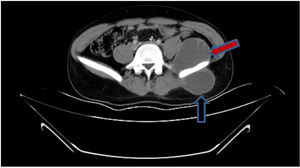

Diagnosis and evolutionIn detailed medical history, there was a positive history of tuberculosis (TB) in his family. Hemocultures were sterile. Computed tomography revealed a mass causing significant bone destruction on manubrium sterni and extending to the anterior mediastinum (Fig. 2). In addition, vertebral osteomyelitis was observed, showing enhancement of L1, T12, T11, T10, T9, and T8. Abdominal scan demonstrated a psoas abscess measuring approximately 66mm×45mm and a gluteal abscess measuring 40mm×56mm (Fig. 3). Due to the lack of improvement, the sternal mass was surgically removed. The routine bacterial cultures were repeated but remained sterile. A tuberculin skin test was positive (induration=20mm). Tuberculosis culture was not available and therefore could not be performed. Polymerase chain reaction (PCR) of the excised tissue was positive for TB. The biopsy disclosed necrotizing granulomatous inflammation which was consistent with TB. A diagnosis of TB was made and quadruple anti-TB drugs including isoniazid, rifampin, pyrazinamide, and ethambutol were initiated. The abdominal abscess was drained completely. A material also tested positive for TB via PCR. The drugs were administered for 9 months. The patient has been doing well for 3 months and no recurrence.